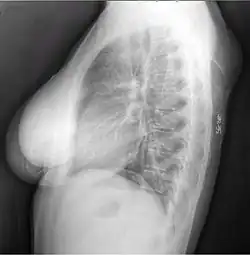

X-ray of a lipoma -

X-ray showing lipoma -